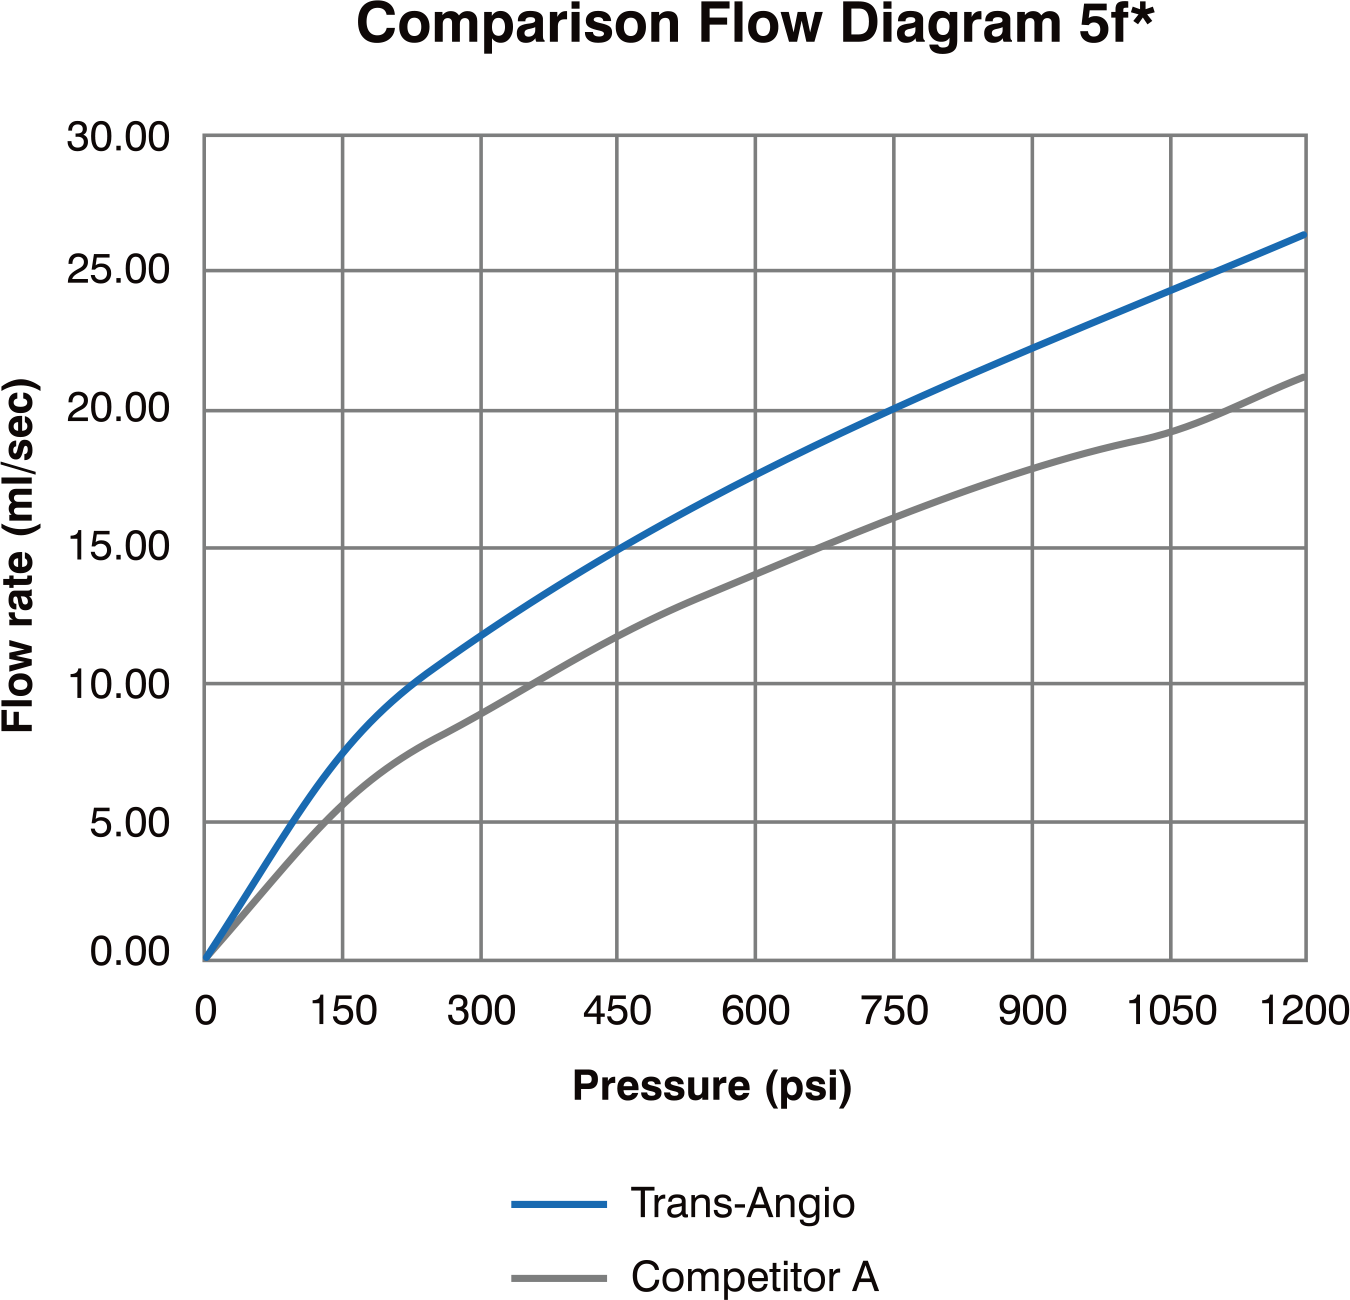

Radial Diagnostic Catheter

Features & Benefits

-

Enables angiography of both RCA and LCA with one catheter that can potentially:

• Eliminates a catheter exchange step

• Shorten procedure & fluoroscopic time

• Lower cost per procedure - Engages with simple clockwise & counter clockwise rotation

- Soft tip reduces potential for vessel trauma

- High Flexibility

- Superior Surface Smoothness

- Excellent 1:1 Torque Control due to double wire stainless steel braiding

- Large inner lumen for superior flow rates

- Atraumatic soft tip

- Guidewire Compatibility : 0.038”/ 0.97mm

- Max Pressure : 1200 PSI / 84 bar